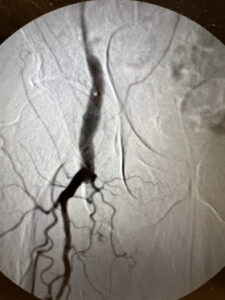

Ενδαγγειακή αποκατάσταση απόφραξης της επιπολής μηριαίας αρτηρίας

ελάχιστα παρεμβατική μέθοδος

24 ωρη παραμονή

Ενδαγγειακή επαναγγείωση της επιπολής μηριαίας αρτηρίας

πλήρη ύφεση της συμπτωματολογίας